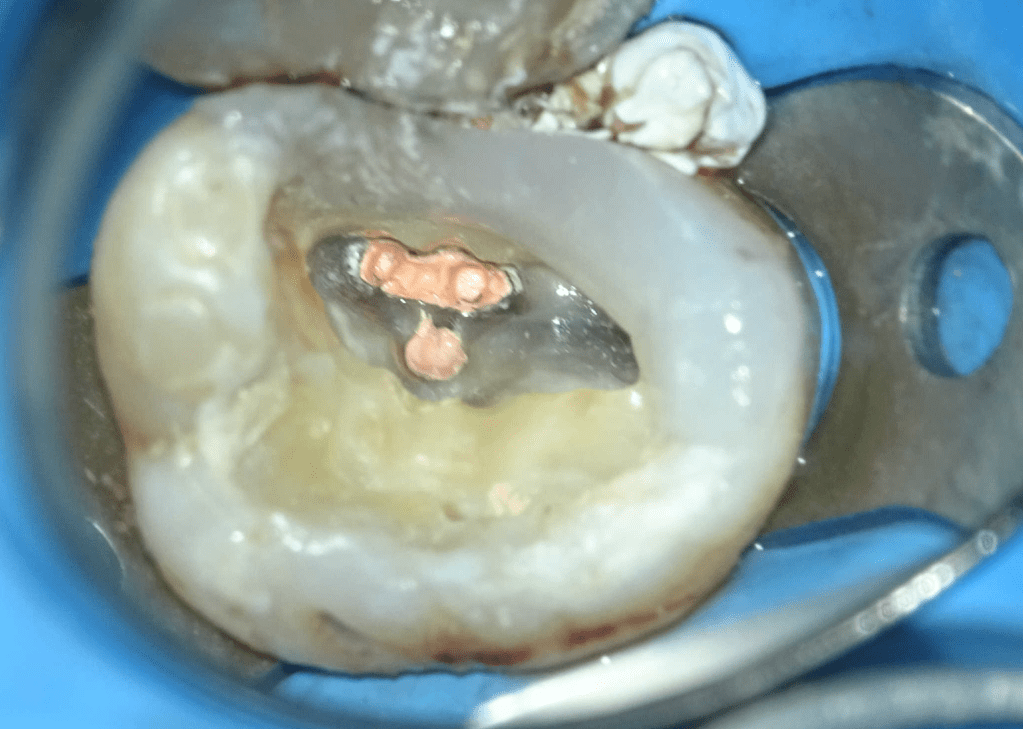

Pulpotomía biodentine + reco preendio